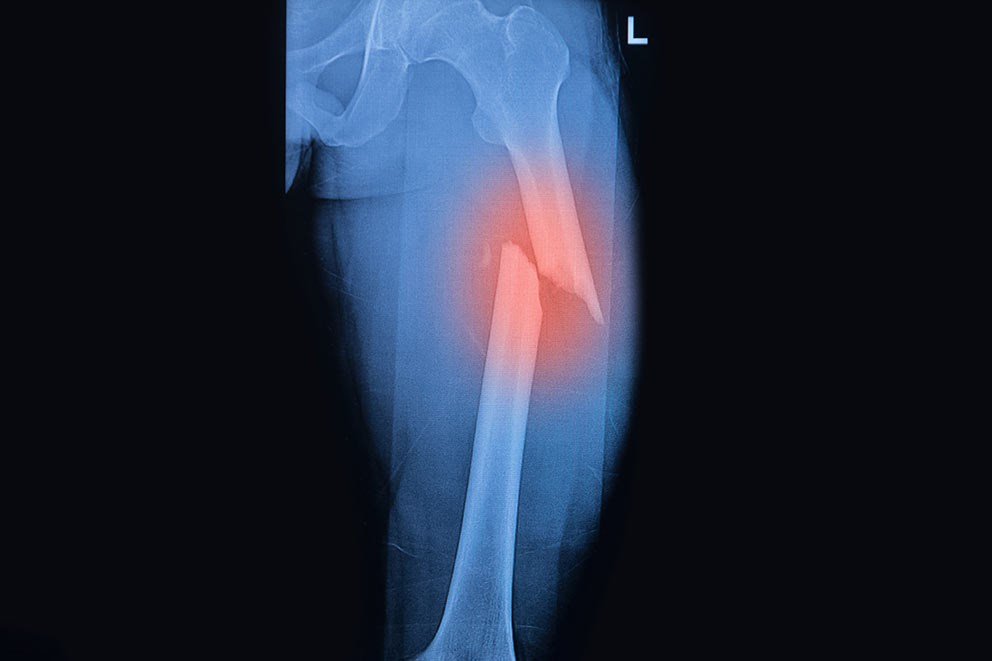

Closed Fracture

When the fracture has no communication with the external air is called closed fracture.

Types of simple fracture:

A) According to Tschereme, 1984, closed fracture divided into the followings,

1) Grade 0: A simple fracture with little or no soft tissue injury.

2) Grade 1: a fracture with superficial abrasion or bruising of the skin and subcutaneous tissue. 3) Grade 2: a more severe fracture with deep soft tissue contusion and swelling.

4) Grade 3: a severe injury with marked soft tissue damage and a threatened compartment syndrome,